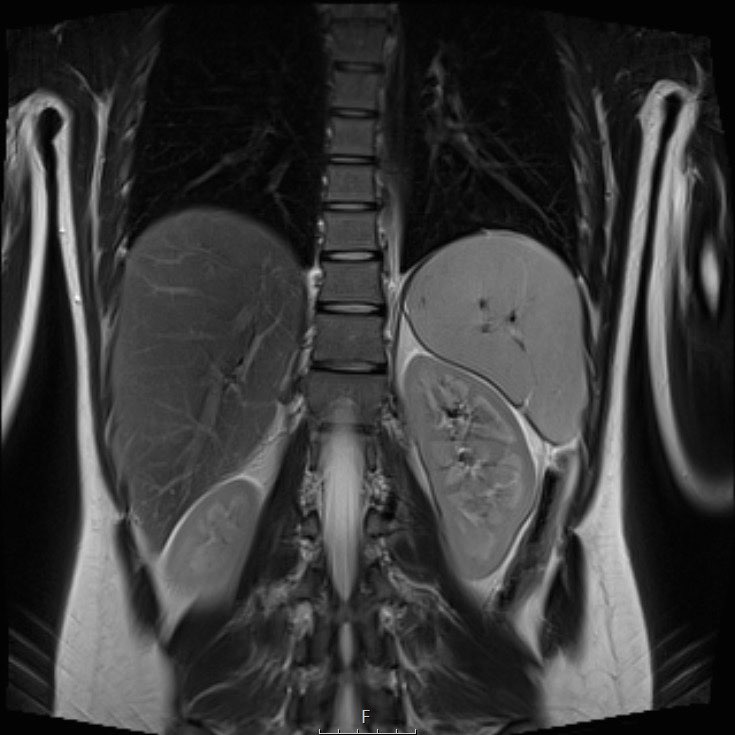

Hình ảnh

U nguyên bào thận ở thận trái của bé trai ba tuổi. Phần còn lại của thận trải dài trên khối u (dấu hiệu “móng vuốt” mũi tên). Khối u khá đồng nhất với một số vùng nang.

Continue with the MRI.

U nguyên bào thận ở thận trái của một bé trai ba tuổi. Khối u thùy đôi nằm ở vùng cực giữa. Có một đài thận giãn ở cực trên (mũi tên).

U nguyên bào thận thường không đồng nhất, với tín hiệu giảm trên T1 và tín hiệu tăng trên T2. Các vùng hoại tử dạng nang thường hiện diện.

Tăng cường tín hiệu sau tiêm Gadolinium không đồng nhất và kém hơn so với sự tăng cường của nhu mô thận bình thường.

Các phần đặc của khối u sẽ cho thấy khuếch tán hạn chế. Xuất huyết thường gặp. Các vùng xuất huyết cũng sẽ cho thấy khuếch tán hạn chế, vì vậy hãy quan sát trên hình ảnh T1 để tìm dấu hiệu chảy máu.

MRI có thể hiển thị rõ ràng huyết khối u trong tĩnh mạch thận và tĩnh mạch chủ dưới, cũng như tình trạng hạch bạch huyết to. Phương pháp này cho phép đo lường khối u một cách chính xác và có thể lặp lại trong các lần khám ban đầu và theo dõi.